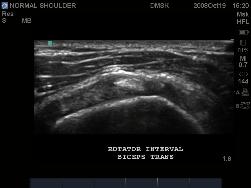

Biceps Tendon at the Rotator Cuff Interval

Normal image of Rotator Cuff Interval.